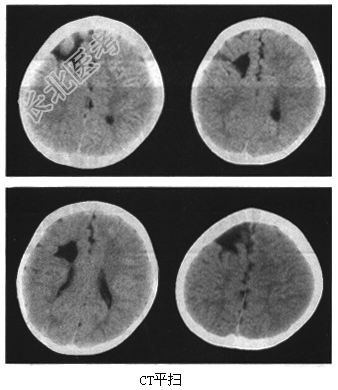

- [材料题] 患者,女,8岁。因为癫痫、智力低下来院检查,影像学检查如下图。

- 简答题1、请问该患者的诊断是什么?

- 简答题2、请问该病常见的临床表现是什么?

- 简答题3、请问本病的特点是什么?